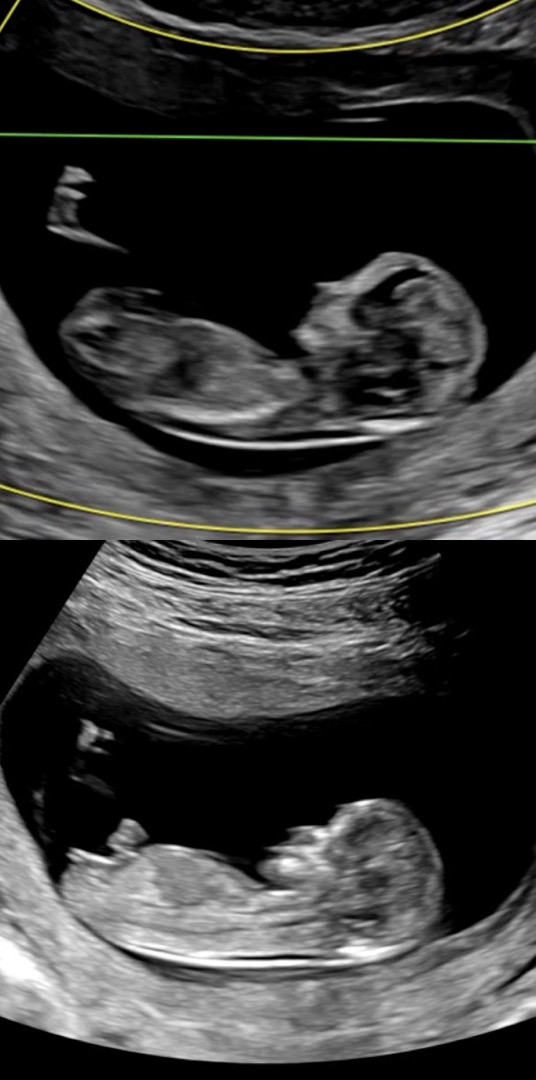

아기 각도법 성별 궁금합니다

투표 해주세요^^

제가 딸은 잘 봐서요... 딸 99% 같아용 ㅎㅎ